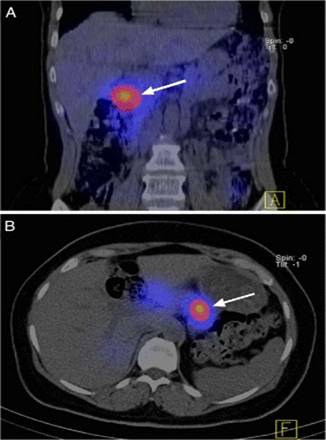

Hình minh họa: Ghi hình SPECT/CT với 111In-DOTA-exendin-4 cho thấy hình ảnh U –insulin trong tuyến tụy